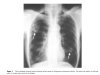

雖然人不是迭宮絛蟲的最終宿主,但裂頭蚴在人體裏可不會老實待着,它會在人體不同部位間到處亂竄,給身體帶來各種傷害,帶來的損傷可能遍佈全身。由裂頭蚴引起的疾病統稱為裂頭蚴病,根據發病的部位,又可以大致劃分為眼、皮下、口腔面部、腦和內臟五大類。

在中國,眼裂頭蚴病的發病率最高,症狀也頗為恐怖,病人的眼部會出現腫塊並伴隨各種嚴重不適。如果裂頭蚴侵入的部位是眼球,甚至可能導致失明。更可怕的是,裂頭蚴還會侵犯大腦,嚴重時可能讓人癱瘓。